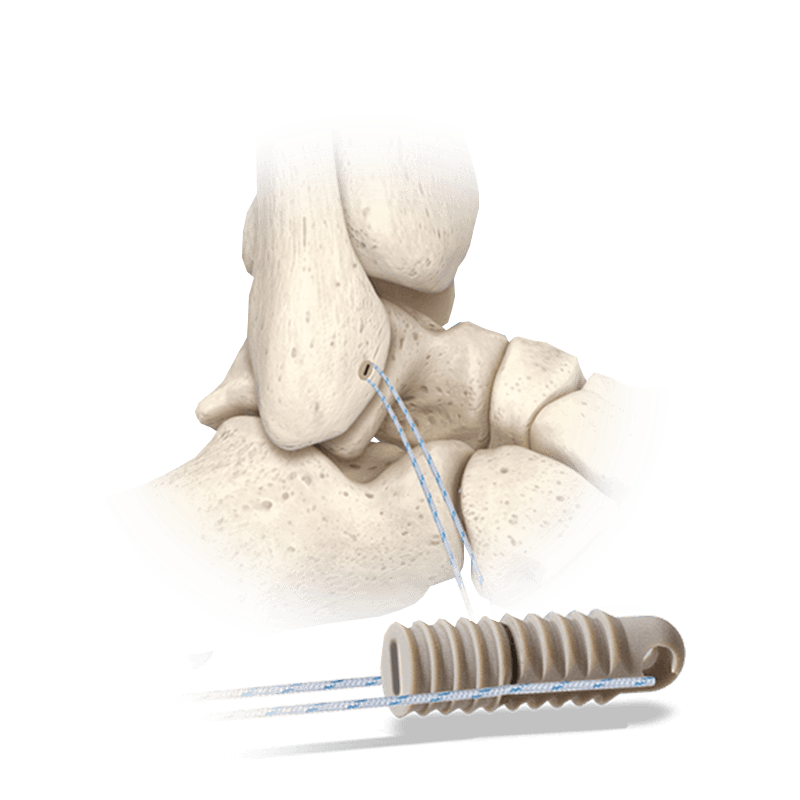

PEEK anchor with unique suture channel that allows surgeons to implant, tension, and lock the anchor

Versatile anchor useful in a variety of procedures